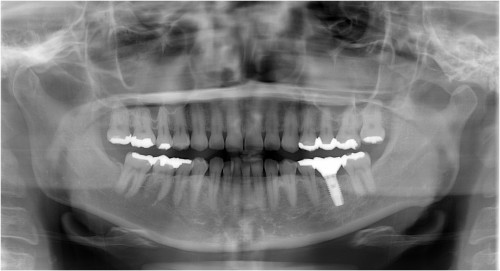

術後

被せ物装着